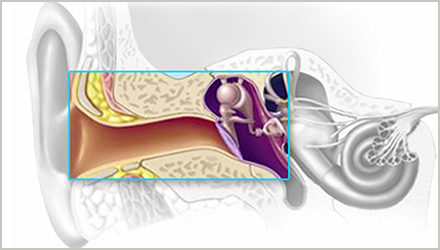

传导性听力损失指的是病变存在于外耳或中耳,使得声音在抵达内耳之前受到阻碍。

1. 中耳置管术

耳部炎症高发于儿童。根据美国耳鼻咽喉头颈外科学会的统计,孩子在5岁以前至少有过1次耳部炎症。 耳部炎症通常会自行消失且不会造成永久性损伤,但部分儿童患有慢性中耳炎,久而久之导致听力下降,学习成绩不佳,出现行为或言语障碍。

通常这种情况下,医生会建议通过手术,在耳内放置中耳管或压力平衡管,缓解中耳积液无法排出的情况下鼓膜增加的压力。

短期管通常在6至18个月内自行脱落,而长期管放置时间稍长并需要专业耳鼻喉科医生拔除。

2.镫骨切除术

正如动脉粥样硬化会引起动脉硬化一样,耳硬化指的是中耳镫骨底板上出现了异常硬化,从而出现听力下降。

目前耳硬化症的治疗方法主要是手术,其中镫骨切除术是公认的治疗方法:

将出现异常硬化的镫骨部分或全部切除,用自体的残余镫骨,或自体其它处的骨或软骨小柱、各种有机无机材料制成的人工镫骨,置于砧骨长突与前庭窗之间代替镫骨。